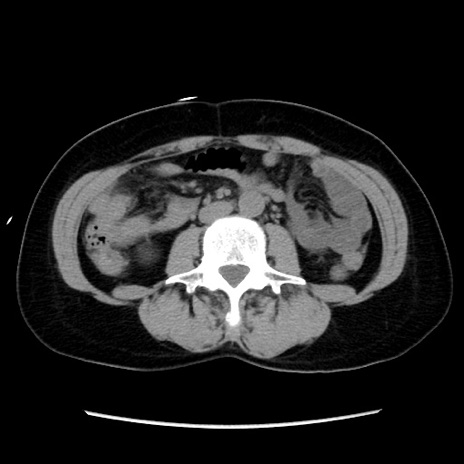

冠状断像